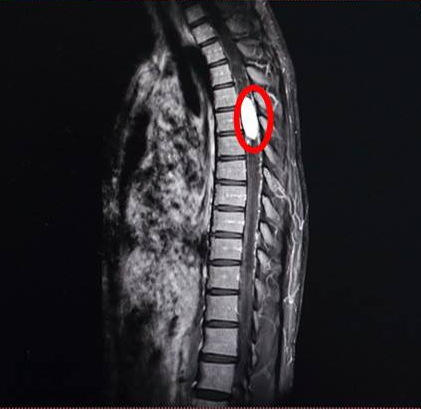

脊髓腫瘤,也稱椎管內(nèi)腫瘤,約占中樞神經(jīng)系統(tǒng)腫瘤的15%,髓外以神經(jīng)鞘瘤較多見,其次為脊膜瘤;髓內(nèi)占位病變以室管膜瘤較多見,其次為星形細(xì)胞瘤。椎管內(nèi)腫瘤性質(zhì)多為良性。

對于脊髓或神經(jīng)壓迫產(chǎn)生癥狀的椎管內(nèi)腫瘤,摘除腫瘤是當(dāng)前更切實合適的治療手段。其中,椎板切除術(shù)是解決脊髓腫瘤的常用外科手段之一。